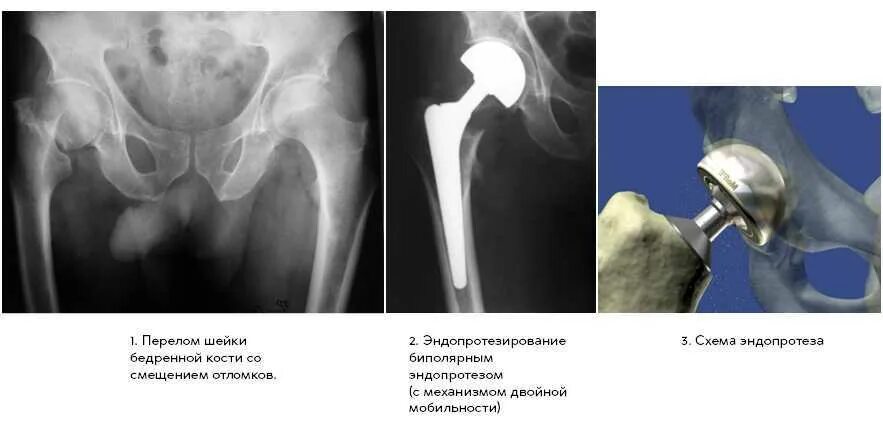

Перелом шейки бедра сколько живут пожилые